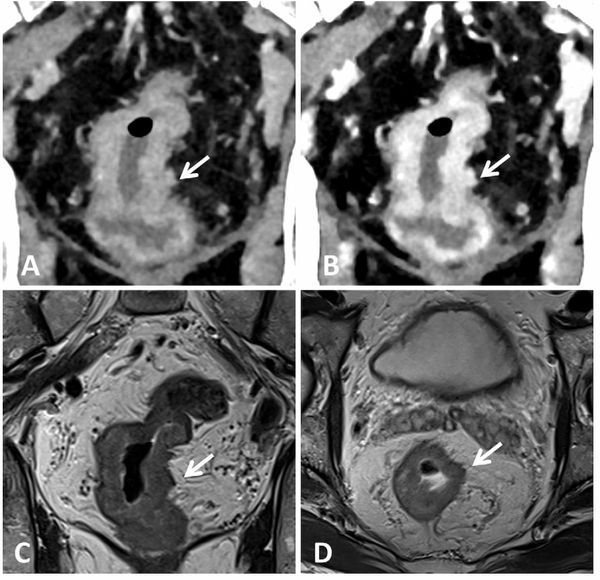

In a prospective comparison with prior criteria for evaluating hepatocellular carcinoma surveillance, the American Association for the Study of Liver Diseases (AASLD) version 2023 system offered significantly higher sensitivity.